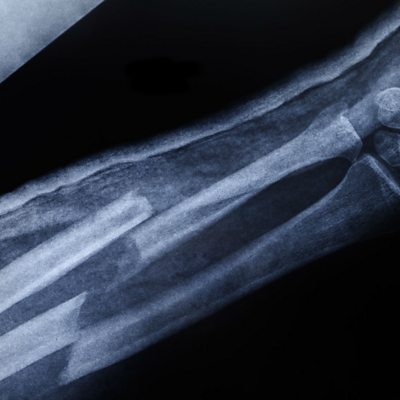

It takes just 10 days to create new bone using animal cells. Yutong Li and Azadeh Rezaei, PhD students from University College London in the UK, are hoping to develop the technique so it can be used to regenerate bones in elderly patients. (Image: Broken arm x-ray Credit: Getty Images)